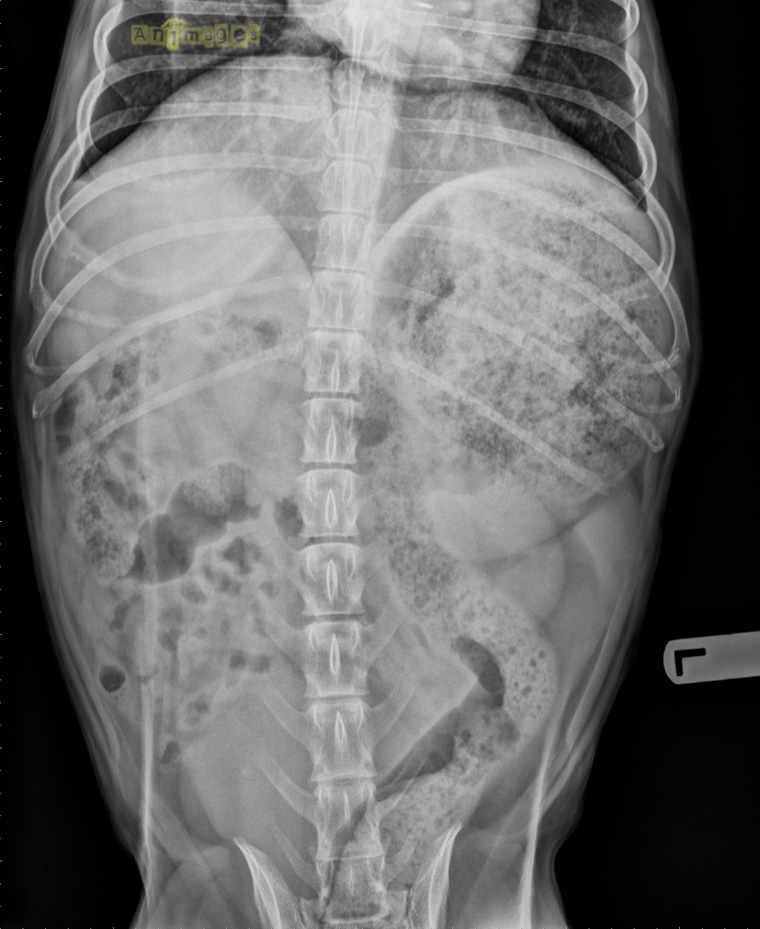

VD_animages